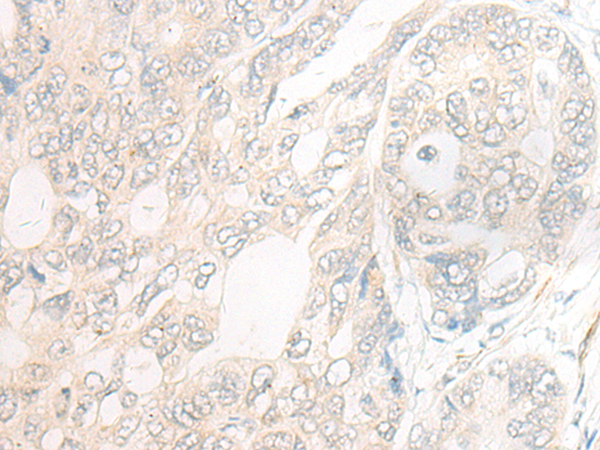

分类: 科研抗体货号: P06441别名: PC; APC; PROC1; THPH3; THPH4应用: WB,IHC反应种属: Human